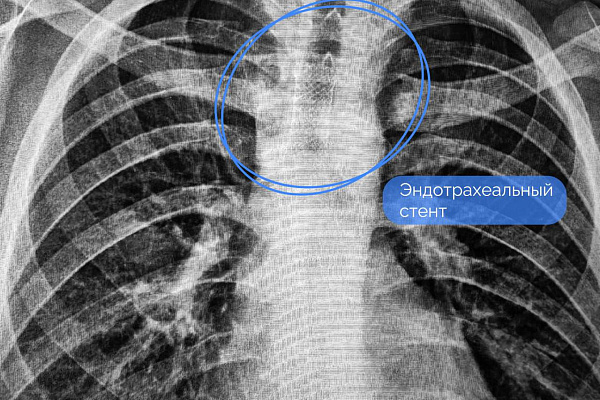

Наши врачи решили не подвергать юного пациента дополнительной хирургической агрессии и обойтись малоинвазивной и абсолютно бескровной методикой. Через естественные дыхательные пути установили эндотрахеальный нитиноловый стент с защитным покрытием. Он перекрыл дефект, лёгкое сразу расправилось и начало выполнять свои функции. Но на восстановление целостности стенки трахеи за счёт рубцовой ткани потребовалось время. Устройство извлекли через три недели, убедившись в успешном результате лечения. Подросток выписан без ограничительных рекомендаций.